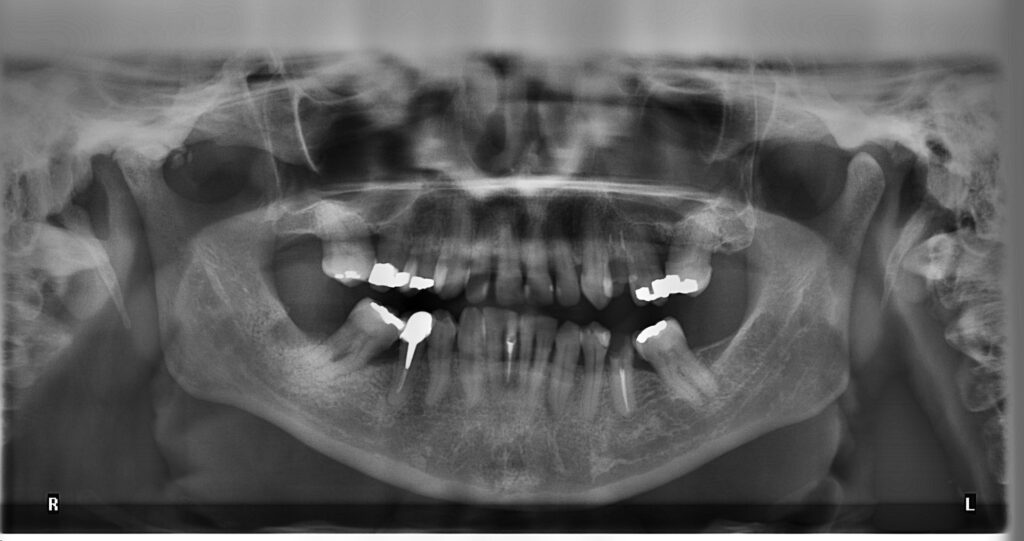

Digital XRays and Panoral Radiographs Westside Family Dentistry Dental X Rays Dangerous Your radiation dose for one dental x ray has to be 500 times more than your daily recommended dose in order to cause any harm. By following recommended guidelines for. Cnn’s elizabeth cohen has tips for deciding if. But they can penetrate your body, accumulate over time, and. Although it is true that a small amount of radiation does go. Dental X Rays Dangerous.